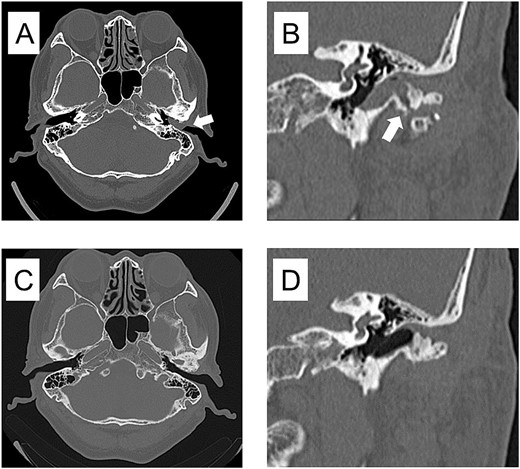

Based on these findings, a clinical diagnosis of TMJ osteoarthritis and TMJ ganglion was made. In July 2017, the mass in the external auditory canal ruptured, and the swelling disappeared; however, the mass flared up again in September, and in October 2017, the left external auditory canal was completely occluded. Axial-section CT showed occlusion of the left external auditory canal, and coronal-section CT showed a bone defect extending from the TMJ to the external auditory canal. (Fig. 4A, B). The patient requested surgery and underwent a left-sided mandibulectomy under general anesthesia and auditory canalplasty performed in December. Intraoperatively, the TMJ was approached via a left preauricular incision, the joint space was opened, and the mandibular head was removed via an 8-mm horizontal osteotomy. During surgery, the surrounding calcified material was removed, as was the anteriorly dislocated articular disc because it was deformed (Fig. 5). Subsequently, transcanal endoscopic ear surgery was performed by otolaryngologist. A skin incision was made before the mass, and a clear jelly-like fluid was found. After the surgery, the patient had intermaxillary fixation for 3 days and began opening training on the fourth day. The opening size improved to 48 mm on the 10th day, and the patient was discharged 13 days after the surgery.

CT imaging findings when the mass was enlarged and the ear canal was obstructed and 3 years after surgery. (A) Axial section CT shows occlusion of the left external auditory canal. (B) Coronal section CT shows a bone defect from the temporomandibular joint to the external auditory canal. (C) Axial section of postoperative 3 years CT shows resolution of the mass in the external auditory canal. (D) Coronal section of postoperative 3 years CT shows restoration of bone defects from the TMJ to the external auditory canal.